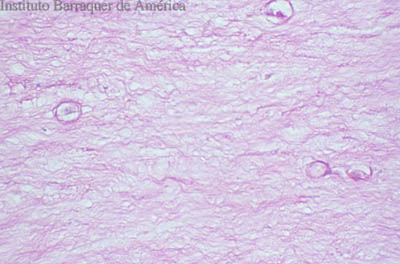

Tinción PAS

(Acido Periodico de Schiff)

Magnificación 160x

Magnificación 160x

Tejido corneal Procesado

PAS

PAS